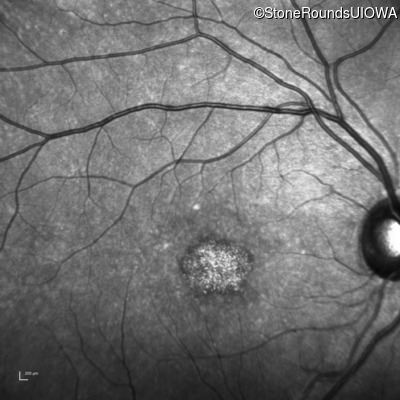

Infrared Fundus Photograph - Right - 20/160 +1

Exemplar

Infrared Fundus Photograph - Left - 20/125 -1